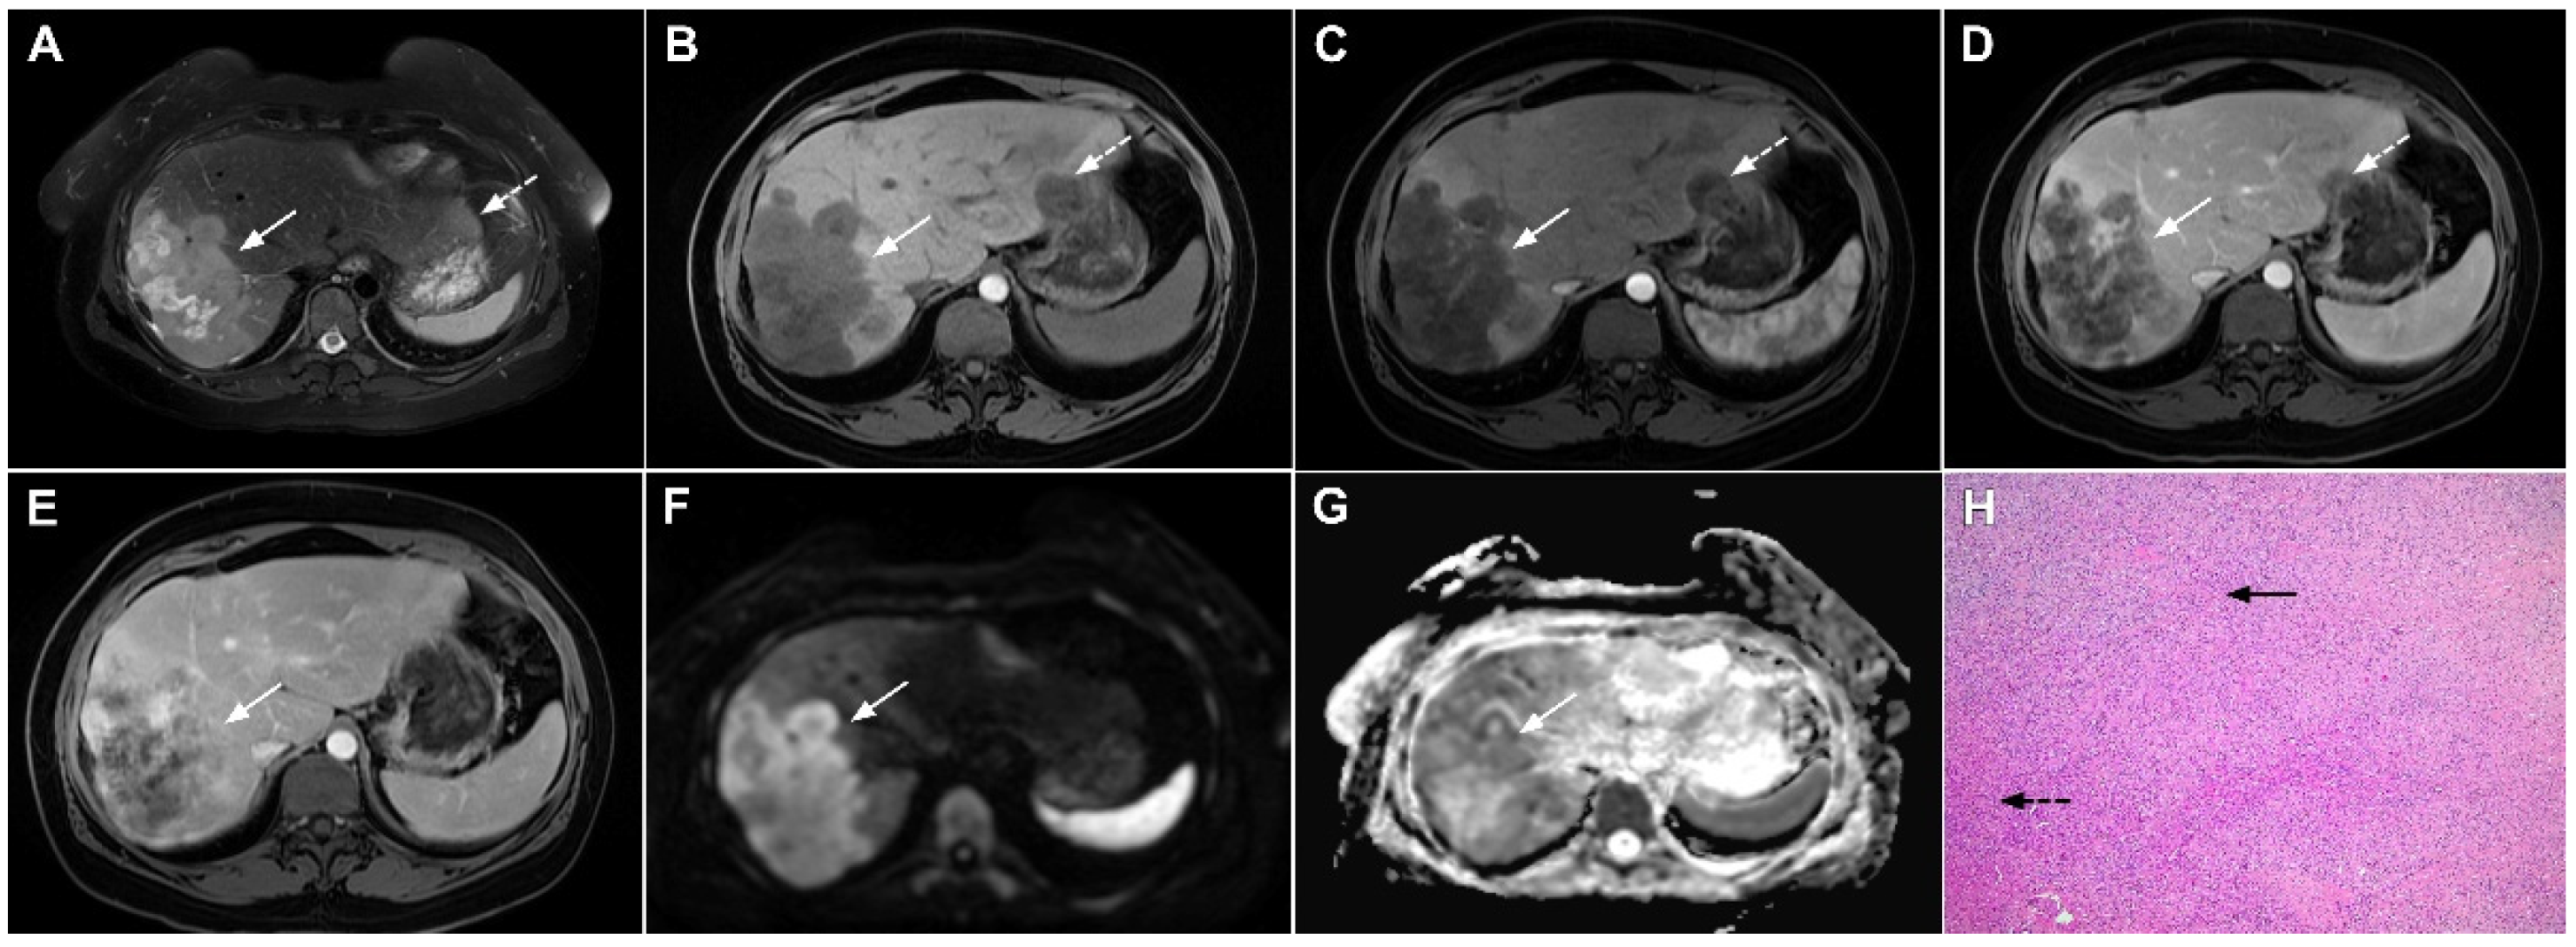

Figure 6.

Hypervascular mass-forming cholangiocarcinoma in a 63-year-old woman. The axial T2-weighted image (A) shows a moderately hyperintense tumor (arrow) located in liver segments VI and VII with a subtle medial capsular retraction. The lesion (arrow) is hypointense on the plain T1-weighted image (B), hypervascular in the arterial phase (C) with washout on the portal venous phase (D). The tumor (arrow) is hyperintense on DWI (E). Hematoxylin and eosin (H&E) staining (F) showed well-differentiated cholangiocarcinoma (arrow) surrounded by normal liver parenchyma (dashed arrow); original magnification ×40.